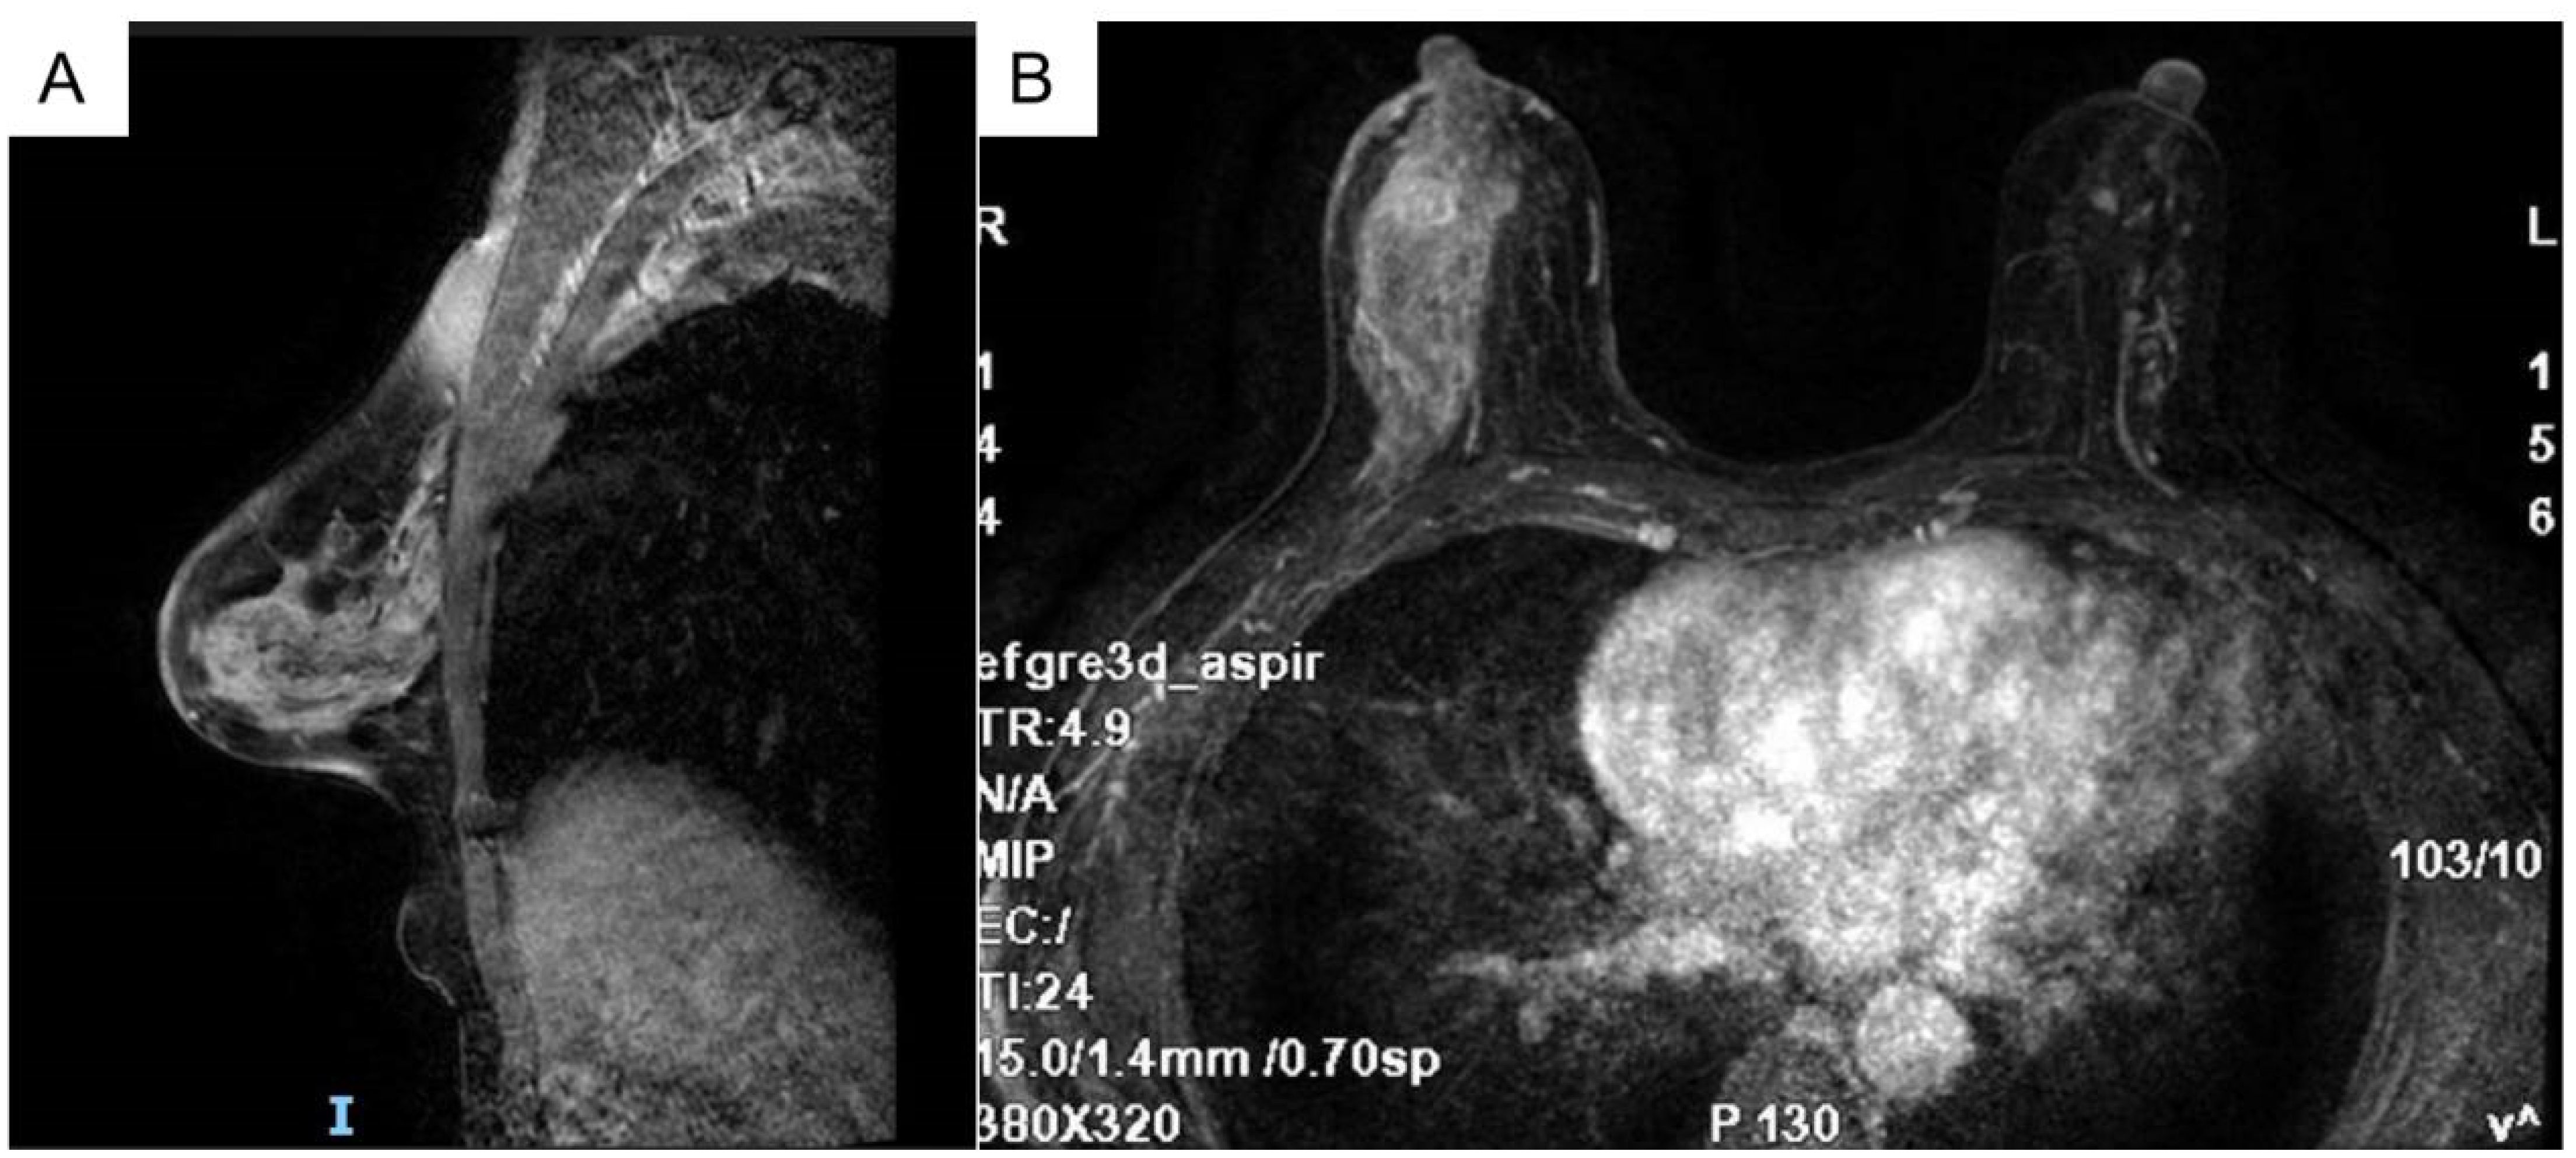

The breast MRI (Figure 1), both with and without contrast administration, identified C-type bilateral breasts with low background enhancement. The outer quadrant of the right breast exhibited multiple areas of abnormal enhancement, nearly including the entire region. Following contrast injection, enhancement appeared markedly irregular, with a significant increase in vascular shadows both within and around the affected areas. The time-signal intensity curve conformed to type II, while diffusion was restricted (1.1). Enlarged lymph nodes in the right axilla, accompanied by surrounding edema and high signal diffusion, indicated multiple regions of abnormal enhancement in the right breast and enlarged axillary lymph nodes.

Figure 1

MRI images of breast tissue. Panel A shows a sagittal view, highlighting internal structures and varying tissue densities. Panel B provides an axial view, displaying the breast and surrounding tissues with distinct areas of brightness and darkness signifying different tissue types.

Figure 1. Bilateral breast c-shaped images with low background enhancement and multiple regional abnormal enhancement areas in the right lateral quadrant of the breast [(A) Sagittal section (B) Transverse section].